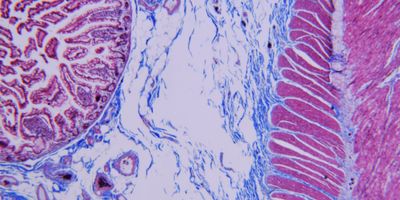

Interlaboratory inconsistency in IHC adversely affects the quality and standard of patient care